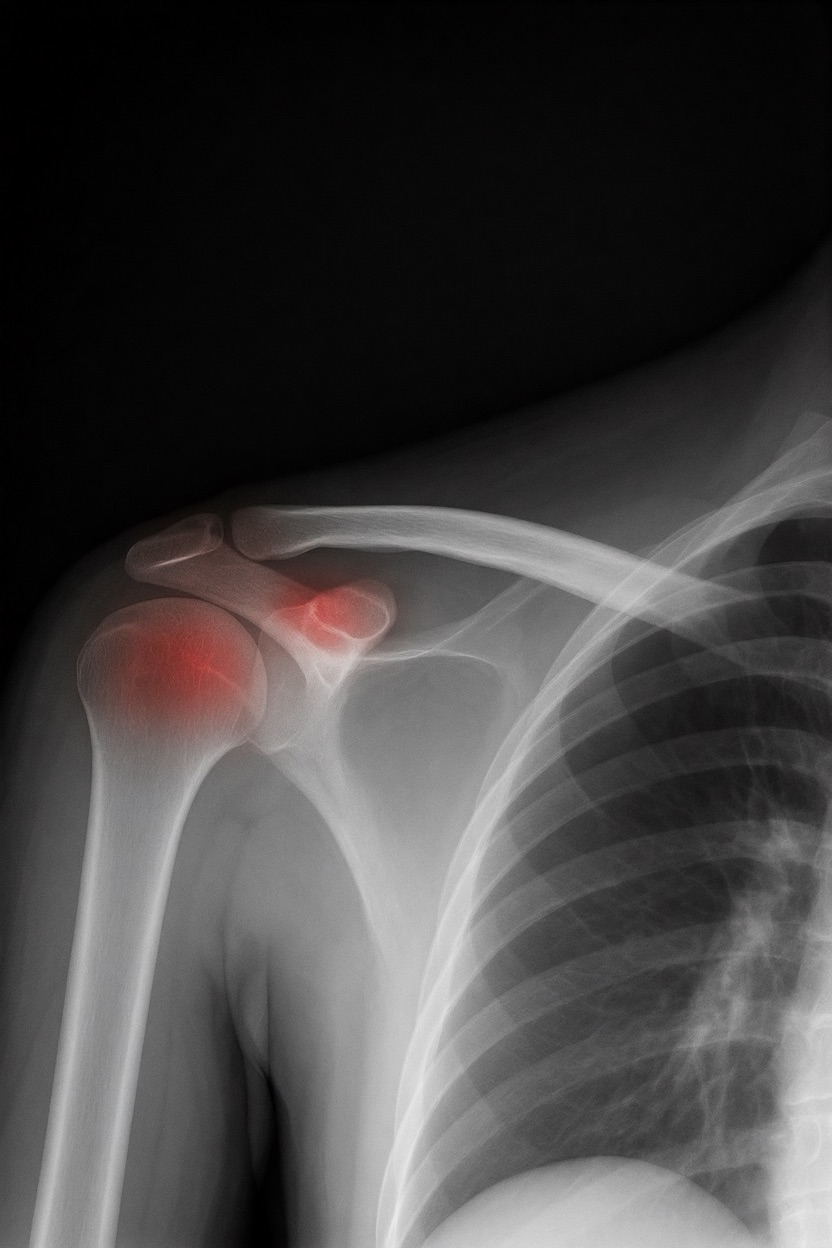

アートや写真の編集用に設計されたFlux Kontextのようなモデルを、医療画像、たとえば「単純な」骨折の赤色マーキングに使用できるか?

即答:面白い結果を出すが、過剰に反応し、医療ツールとしては信頼性に欠ける。これはアイデアを試すためのプロトタイプに過ぎない。

テスト結果:

- 偽陽性 ≈ 24%

- 骨折検出 ≈ 20%

感度モード(検出を優先、ノイズ多め)

- Euler、15ステップ、Karras

- Denoise:1.0

結果:

- 偽陽性 ≈ 80%

- 骨折検出 ≈ 86%

さらに攻撃的な設定(例:rk beta57、Denoise 1.0)では、**偽陽性100%、検出100%**という馬鹿げた結果に:すべてを赤で塗りつぶし、健常部もほぼすべて骨折と誤認する。未経験の目には区別がつかない。

Civitai用に作成した、100% AI生成の合成ミニデータセット(健康なX線10枚、骨折のあるX線10枚)でテスト:

- 健康な骨での偽陽性:100%

- 骨折検出:≈ 45%